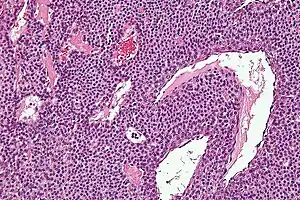

Histologicamente, tumores glômicos possuem uma arteríola, uma anastomose e uma vênula. Tumores glômicos são células de músculo liso modificadas que controlam a função de termorregulação da derme. Essas lesões não deve ser confundido com paragangliomas, que já foram equivocadamente chamados de tumores do glômicos. Tumores glômicos não surgem a partir de células glômicas, mas os paragangliomas sim.